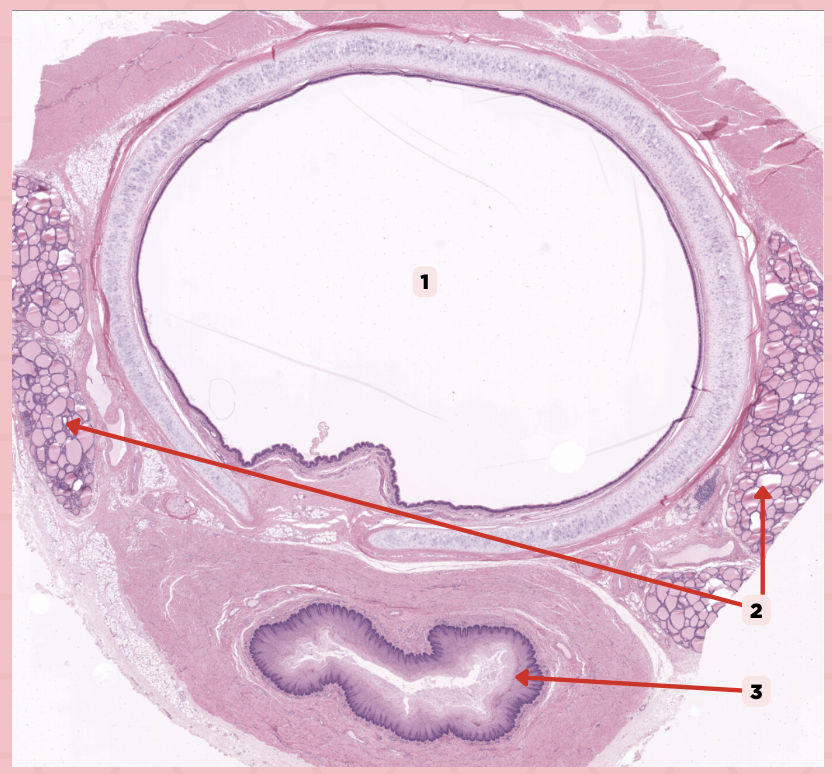

Lumen

It is a large ovoid space that occupies the center of the trachea.

Thyroid gland

This consist of cystic structures that contain highly eosinophilic material on either side of the trachea.

Lumen

Identify the structure labeled as 1.

Thyroid Gland

Identify the structure labeled as 2.

Esophagus

Identify the structure labeled as 3.

Ciliated Pseudostratified Columnar Epithelium

What is the epithelium of no. 3?

MALT

What type of lymphoid tissue supplies no. 3?